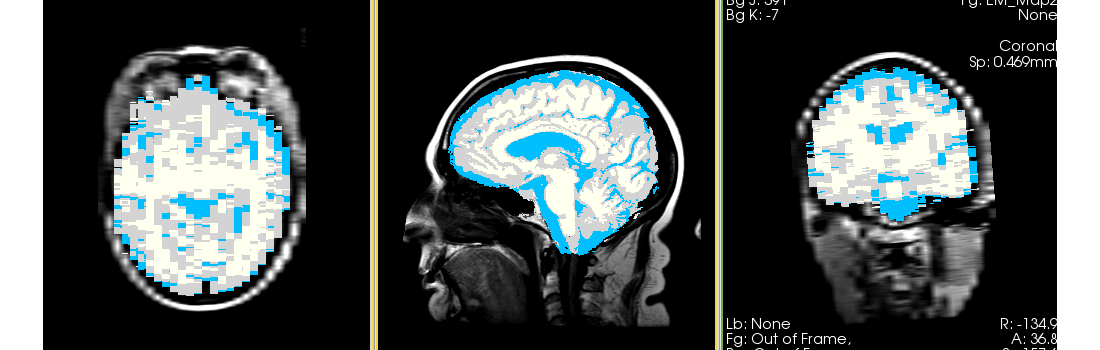

Single channel automatic segmentation of T1 and T2 MRI brain scans into the major tissue classes (gray matter, white matter, csf). The task can be applied to T1 and T2 brain scan showing parts of the skull and neck. The pipeline consist of the following steps:

- Step 4: Automatically segment the MRI scan into the structures of interest using EM Algorithm (Pohl et al 2007)

- intracranial cavity (ICC)

- white matter (WM)

- grey matter (GM)

- cerebrospinal fluid (CSF)